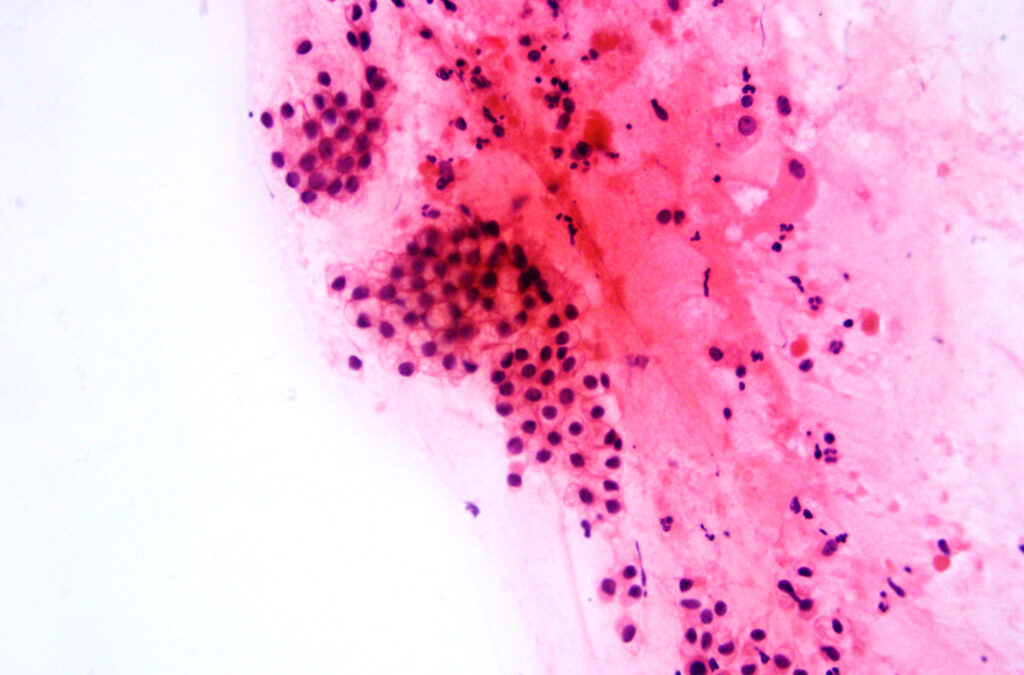

Mujer de 64 años, sin antecedentes clínicos relevantes. La citología cervical convencional reveló células atípicas aisladas o en pequeños grupos planos, con núcleos hipertróficos, hipercromáticos, cromatina densa, ocasionalmente con nucléolos, y citoplasma mal definido por artefactos de fijación. Se observaron figuras de mitosis y un fondo necrohemorrágico, interpretándose como carcinoma escamoso invasor no queratinizante.

La colposcopia con biopsias aleatorias del cuello uterino mostró solo atrofia, sin evidencias de la zona de transformación escamocolumnar. Posteriormente, una biopsia guiada por videohisteroscopía reveló un carcinoma pobremente diferenciado, con sábanas de grandes células de citoplasma claro, núcleos atípicos y pleomórficos, y extensas áreas de necrosis. Se planteó inicialmente carcinoma escamoso indiferenciado. Sin embargo, las células neoplásicas fueron positivas para CK7, vimentina y NAPSIN A, y negativas para p63, receptores hormonales y p16. Estos hallazgos permitieron el diagnóstico de adenocarcinoma endometrial de células claras (pT2, pN0). La revisión retrospectiva del frotis cervical reveló células con citoplasma variando de opaco a finamente vacuolado, característico del adenocarcinoma de células claras.

Las células del carcinoma endometrial de células claras son voluminosas y pleomórficas, con núcleos desnudos en un fondo necrótico. La diferenciación con carcinoma escamoso no queratinizante puede ser difícil solo con citología, requiriendo inmunohistoquímica para su confirmación.